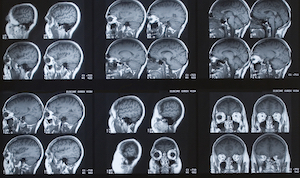

成像测试:医生会给你一个CT扫描或MRI排除任何惊奇的望着中风,脑部肿瘤,或流体积累在大脑中。测试可以显示医生如果你有病变(坏死组织)或小中风的迹象。但是医生喜欢核磁共振成像,给出一个更详细的图片大脑的结构。